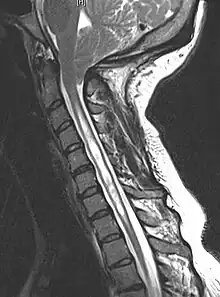

A siringomielia é prontamente diagnosticada com Ressonância Magnética, podendo ou não estar associada à malformação de Chiari.